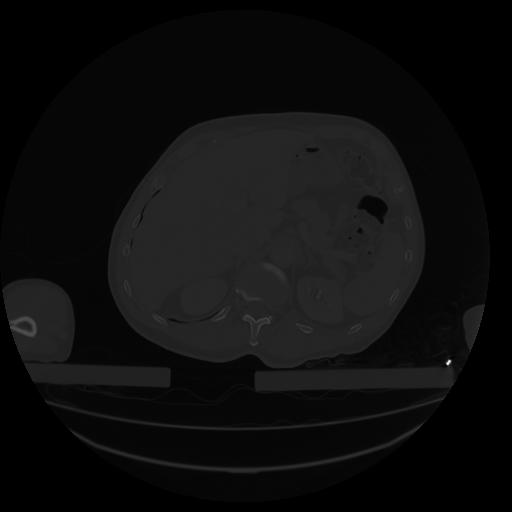

34 CUERPO,CE,Vol,1.0,CUERPO,,